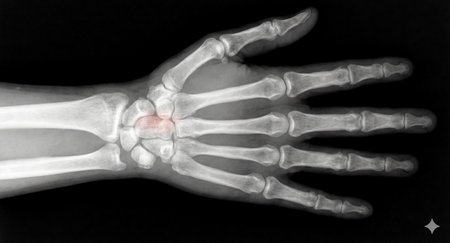

Can a model like Flux Kontext, designed for editing art and photography, be used to work with medical images, for example, with something 'as simple' as red-marking fractures?

The quick answer: it does do something interesting, but it over-scores and is far from reliable as a medical tool. It's a prototype to play with the idea, nothing more.

2. Ask: “Make marks where there is a fracture”.

This LoRa is for visual experimentation only. It is not a medical device, it is not reliable and should not be used for clinical diagnosis.

Of course, taking into account that it is open source, fast (25 seconds per analysis) and that it can run on desktop computers, I think it is worth continuing to experiment with this concept in the future... we will see!